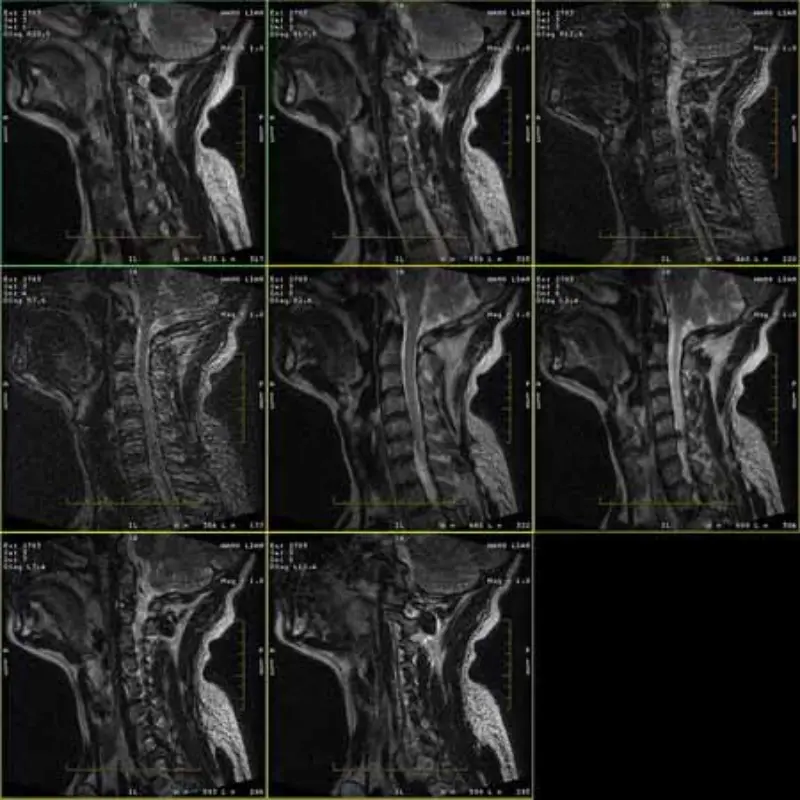

Les images des protocoles FRFSE et GRE présentent des images fantômes et parfois des images à faible SNR apparaissent dans une seule série. Mais les images du protocole SE sont normales.

Veuillez regarder les images jointes.